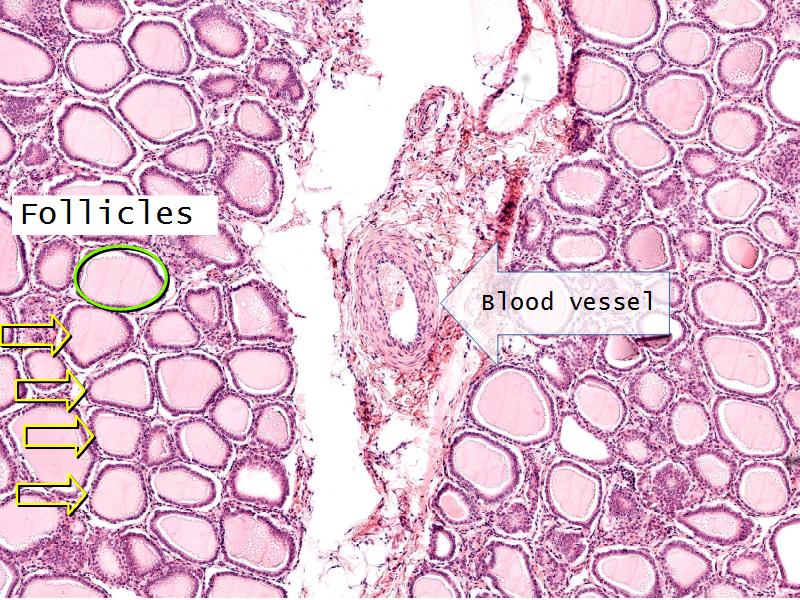

Thyroid gland

Four elements making up the thyroid

Thyroid gland

- Follicle

- Follicular epithelium

- Parafollicular cells

- Colloid